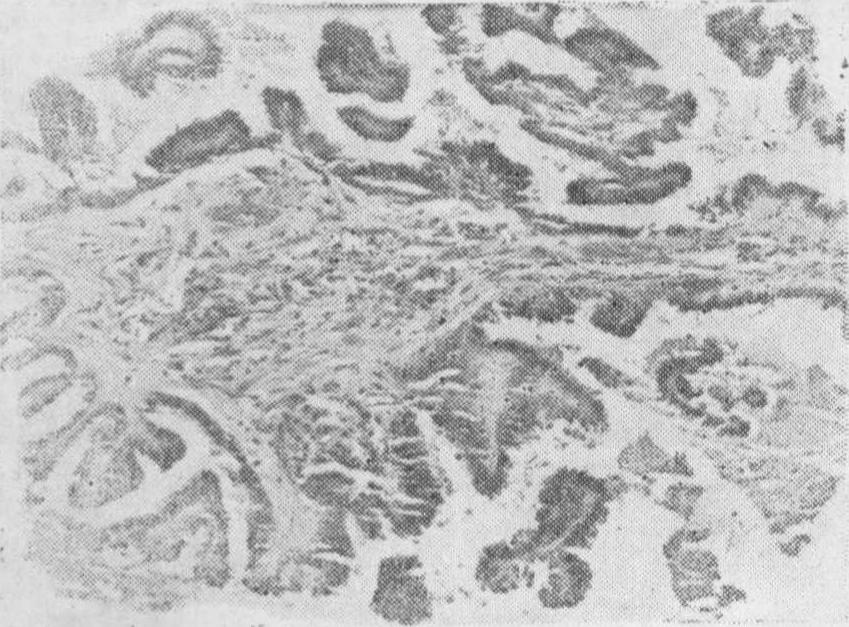

图2 卵巢交界性浆液性乳头状囊腺瘤

交界性浆液性囊腺瘤 是一种在外观上与良性浆液性囊腺瘤无明显区别而在组织学及生物学特性上介于良性与恶性之间的肿瘤(图2)。它可以复发及有大网膜及腹膜种植,但其预后较恶性者好,10年存活率为95%,大体检查,双侧的交界性浆液性囊腺瘤较良性者多见,乳头状物的数目亦较良性者多,有时可穿破包膜达肿瘤表面。镜下可见

❶乳头上皮增生而成上皮簇。

❷上皮细胞呈复层(不超过三层),有轻或中度间变。

❸可见核分裂相,但每高倍视野不超过一个。

❹无肿瘤间质浸润。